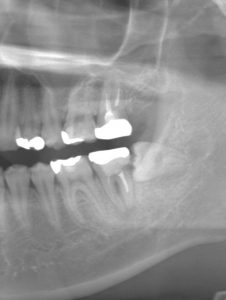

今回は左下の親知らずが横をむいて生えており、そのせいで手前の歯がダメになってしまったケースです。

処置前の写真とレントゲンです。

CTを用いて親知らずの深さや顎の中の神経との位置関係を調べます。

親知らずに大きな虫歯はなく、手前の歯とのサイズも近いことから患者様と相談の上移植をして保存を試みることになりました。